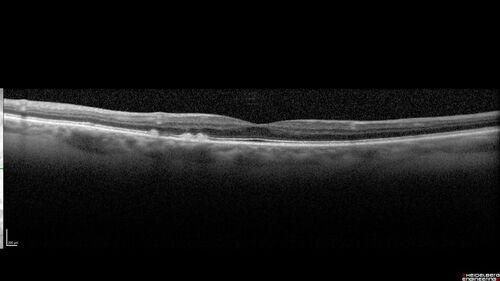

Large Hyper-reflective drusen in age-related macular degeneration

69 year old healthy woman with 20/20 vision and no visual complaints

Large hyper-reflective drusen in AMD